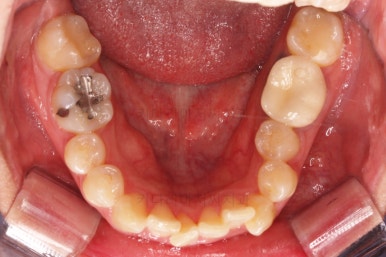

초진 시 입안의 모습입니다.

전반적으로 치열이 삐뚤고, 특정 앞니는 톡 튀어나가 미적으로 좋지 못한 상황이었습니다.

이갈이, 이악물기 습관도 있어서 앞니는 삐뚤어진 채로 치아가 많이 갈려있는 상황이었습니다.

동래교정치과 마무리 사진입니다.

종료 이후에는 어금니의 기존 크라운 보철이 오래되고 탈이나서 재보철을 해주었습니다.

앞니는 비뚠채로 장기간 마모가 되어온 터라 형태가 부적절하긴 한데요.

보철로 마무리하기 보다는 최대한 자연스럽게 시리지 않는 선에서 다듬어 드리고 마무리를 했습니다.